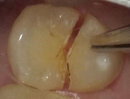

構造の変更:根管治療では、歯の神経を取り除いた後、歯の内部を清掃し、充填しますが、この過程で歯の本来の構造が失われます。結果として、歯の強度が弱まるため、圧力や力がかかると割れる可能性が高くなります。